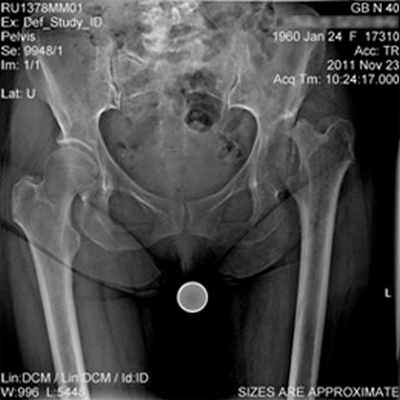

Пациентка В., 51 год, находилась на травматологическом отделение с диагнозом:деформирующий диспластический артроз левого тазобедренного сустава 4 степени с полным вывихом бедренной кости. Асептический некроз головки левой бедренной кости с полным ее лизисом.

Дефект крыши вертлужной впадины. Неоартроз между шейкой левой бедренной кости и крылом левой подвздошной кости выше вертлужной впадины на 3 см. Выраженный болевой синдром. Комбинированная контрактура левого тазобедренного сустава. Дисфункция левой нижней конечности. Все меры реабилитации в данном клиническом примере были бессильны вернуть опороспособность и функцию конечности. Болевой синдром при движениях в суставе был значительным, пациентка вынуждена передвигаться только с дополнительной опорой. Отмечалось значительное укорочение конечности (около 5см).

![]() | ![]() |

Выполнено тотальное эндопротезирование левого тазобедренного сустава в сочетании с костной аутопластикой.